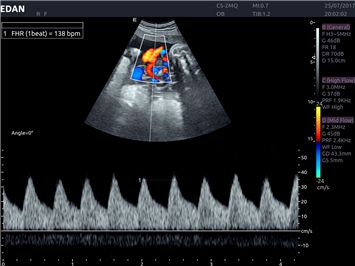

• Акушерства и гинекологии

• Кардиологических исследований

Импульсно-волновой допплер:

Да

Постоянно-волновой допплер: